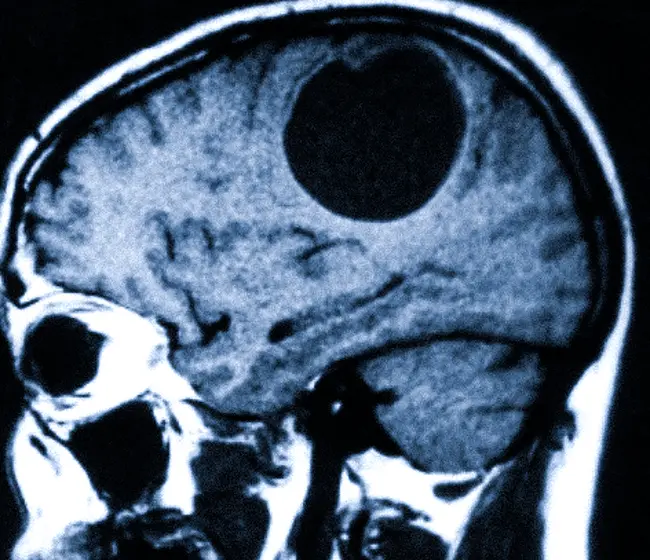

Астроцитома головного мозга на МРТ

Сравнение изображений без контраста и с контрастом: астроцитома мозолистого тела. Отображение опухолей на МРТ может различаться в зависимости от их гистопатологических свойств. Плеоморфная ксантоастроцитома имеет более четкие границы по сравнению с другими видами астроцитом, располагается ближе к поверхности и менее склонна к диффузному распространению.

Небольшая астроцитома и возникшая гигантская киста реактивного генеза. Аналогичная клиническая картина может наблюдаться при абсцессах головного мозга, паразитарных кистах, метастазах и острых ишемических инсультах — все перечисленные состояния требуют дифференциальной диагностики.

Магнитно-резонансная томография также применяется для определения эффективности лечения. На основании изображений можно определить наличие частичного или полного ответа на терапию, стабильное состояние онкологического процесса или его прогрессирование. У пациентов, перенесших резекцию, точное сравнение снимков до и после операции может помочь различить остаточную опухоль и начальную рубцовую ткань на краях резекции. Из-за высокой вероятности злокачественной трансформации диагностику — МРТ головного мозга — всегда проводят с использованием контрастного вещества.

Астроцитомы мозга — это опухоли, которые формируются из астроцитов, поддерживающих клеток нейронов. Они могут быть как доброкачественными, так и злокачественными. Интерпретация МРТ-снимков при астроцитоме требует высококвалифицированного подхода, поскольку опухоли могут иметь различные характеристики и паттерны роста. Зачастую они проявляются как гиперинтенсивные образования на Т2-изображениях и гипоинтенсивные на Т1-форматах, но точная оценка зависит от контрастирования и других факторов.

Для более точной диагностики могут быть использованы дополнительные методы визуализации, такие как ПЭТ-сканирование или КТ. Эти исследования могут помочь в определении метаболической активности опухоли и ее локализации, особенно если есть подозрение на метастазы или другие аномалии.